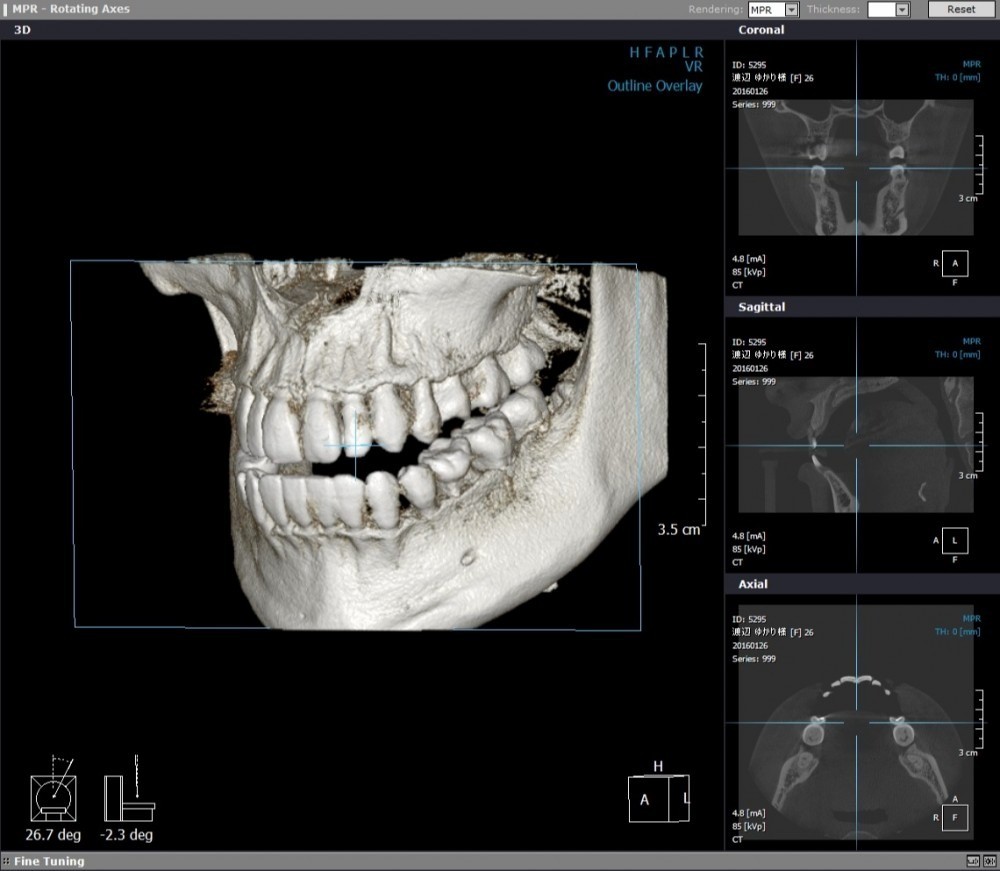

小禄ホワイト歯科では歯科専用CTを完備し、骨の構造を立体的に把握したうえで治療を進めています。さらに、歯肉を大きく切開しないフラップレス埋入法を取り入れ、出血や腫れ、痛みの軽減に配慮しています。

水平埋伏智歯は、歯が横向きに埋まっているため、下顎神経との位置関係が近く、抜歯には高い精度が求められます。小禄ホワイト歯科では3D-CTスキャンを用いた画像診断を行い、歯の根の形や湾曲の状態、下顎神経との位置関係を立体的に把握しています。その結果、より安全性を高め、短時間での抜歯につなげています。